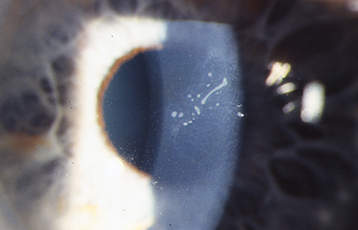

Rare, epithelial dystrophy that is seen in the first years of life, but is usually asymptomatic until middle age. Retroillumination shows discrete, tiny epithelial vesicles involving the whole cornea but can be segmental (see Figure 4.26.3). Although treatment is usually not required, bandage soft contact lenses or superficial keratectomy may be beneficial if significant photophobia is present or if visual acuity is severely affected.

Figure 4.26.3: Meesmann corneal dystrophy demonstrating multiple tiny discrete vesicles in direct illumination.